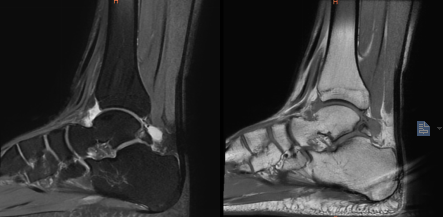

术前MRI显示左踝副骨综合征

一位19岁大学生,由于左踝长期疼痛,辗转多家医院症状未缓解,严重影响其学习生活,经人介绍来到我院骨科治疗。骨科副主任(主持工作)彭李华博士为其进行了全面专业的检查,发现为三角籽骨综合症。完善术前检查及准备后,彭李华博士为患者行“踝关节全内镜下清理、松解术”。患者对手术效果满意,已顺利出院。